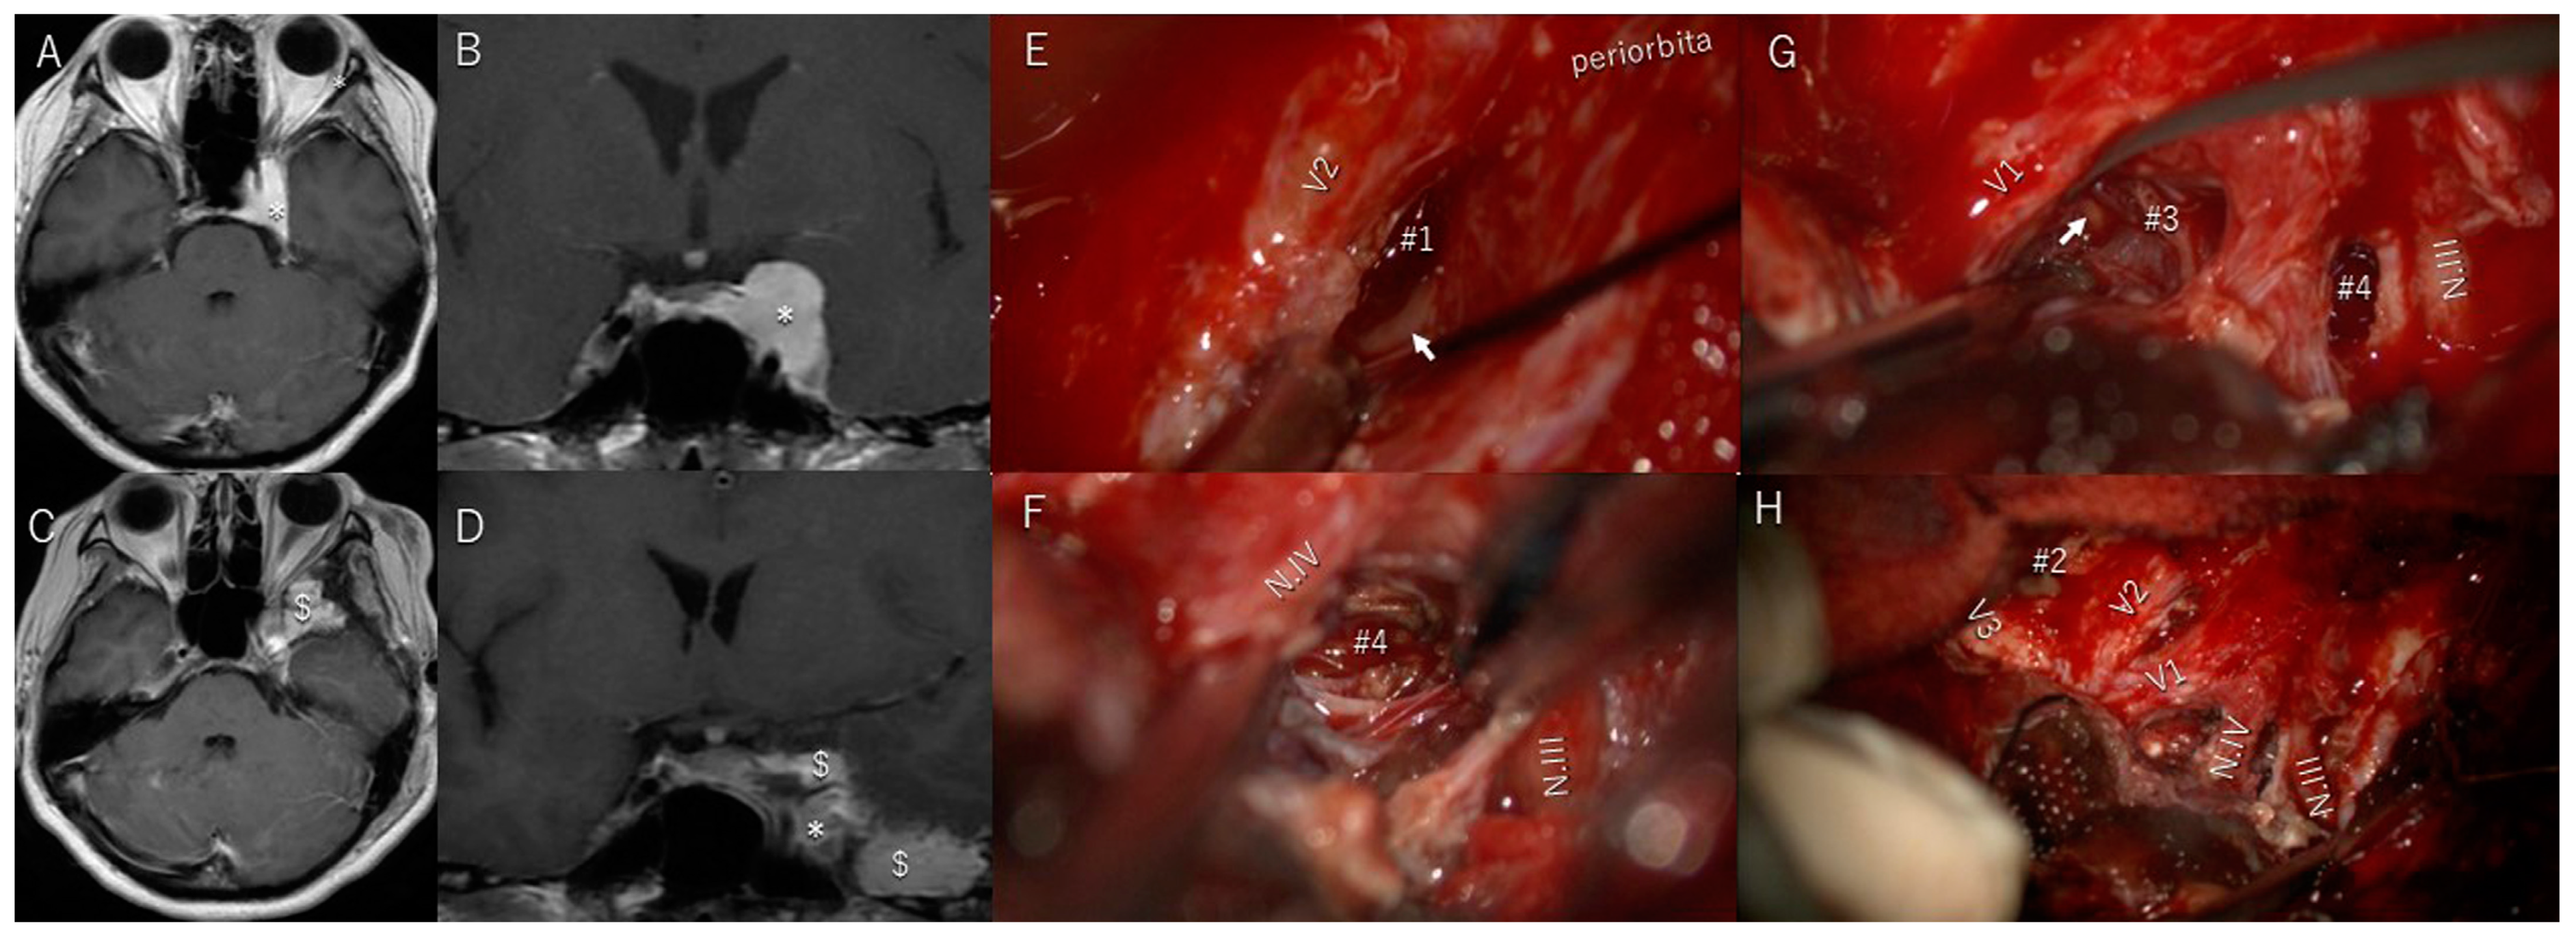

3.6. Illustrative Patient Cases

| 1 | y | y | entire lateral wall of cavernous sinus | Totally with sacrifice of all cranial nerves | 4 | y/no change | y/sacrifice | y/sacrifice | brain stem swelling/complete recovery | |

| 2 | y | y | lateral triangle | Slightly | 4 | y/almost complete recovery | y/complete recovery | y/complete recovery | ||

| 3 | y | y | lateral triangle | Slightly | 3 | y/almost complete recovery | n | n | ||

| 4 | y | y | Parkinson triangle | Slightly | 3 | y/slightly improved | y/complete recovery | n | ||

| 5 | y | n | anterolateral triangle | Totally | 1 | n | n | n | brain swelling/complete recovery | |

| 6 | y | n | Parkinson triangle | Slightly | 4 | y/complete recovery | n | n | brain swelling/complete recovery | |

| 7 | y | n | Parkinson, anterolateral, lateral triangle | Partially | 3 | y/complete recovery | y/complete recovery | y/complete recovery | exophthalmos/complete recovery | |

| 8 | y | n | Parkinson, anterolateral, lateral triangle | Partially | 3 | y/slightly improved | y/almost complete recovery | y/almost complete recovery | facial dysesthesia/almost complete recovery | |

| 9 | y | y | anterolateral, paramedial, lateral, Parkinson triangle | Subtotally | 4 | n | y/complete recovery | y/complete recovery | facial dysesthesia/almost complete recovery | |

| 10 | y | n | Parkinson triangle | Partially | 4 | n | y/worsened. | y/worsened. | ||

| 11 | y | y | paramedial, Parkinson, lateral, anterolateral triangle | Subtotally | 4 | y/complete recovery | n | y/slightly improved | ||

| 12 | y | y | anterolateral triangle, | Partially | 4 | n | y/complete recovery | n | exophthalmos/complete recovery | |

| 13 | y | y | anterolateral triangle | Partially | 4 | n | y/complete recovery | n | ||